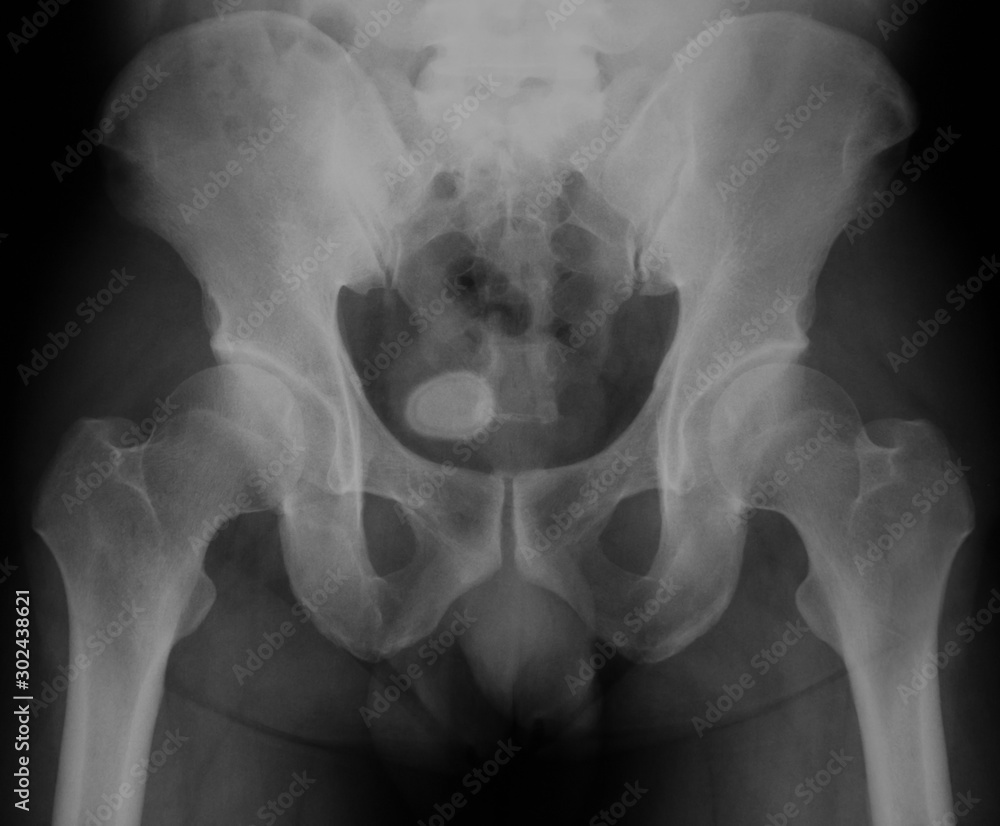

Xray image of urinary system (kidnery, urinary and bladder KUB

Xray image of bladder, Showing bladder stone Photos Adobe Stock Radiolucent Bladder Stones Calcium phosphate stones form in alkaline urine and are typically associated with abnormal metabolic factors, such as hyperparathyroidism and renal tubular acidosis. Scanning in the prone position may be useful to distinguish a calculus impacted at the ureterovesical junction and a stone that has already passed into the bladder. Renal and, specifically, bladder stones made of uric acid have historically. Radiolucent Bladder Stones.